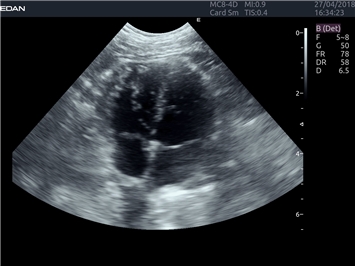

EDAN Acclarix LX4 VET

EDAN Acclarix LX4 VET представляет собой профессиональную ультразвуковую систему, специально разработанную для ветеринарных исследований. Сочетание стабильности, высокой производительности и эффективности делает эту систему идеальным выбором для современной ветеринарной практики.

Передовые технологии визуализации:

Инновационные технологии обработки изображений:

• Адаптивная визуализация тканей:

• Оптимизация изображения для различных видов животных

• Улучшенная детализация структур

• Мультилучевое сложно-составное сканирование (SCI):

• Повышенная четкость изображения

• Улучшенная визуализация сложных анатомических структур

• Технология подавления зернистости:

• Снижение шумов изображения

• Повышение диагностической ценности